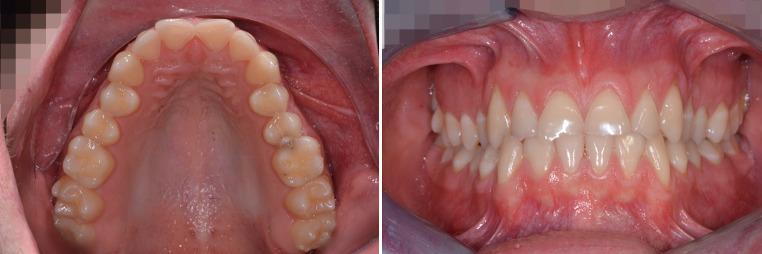

Procedure using CAD/CAM-manufactured insertion guides for purely mini-implant-borne rapid maxillary expanders.

With traditional rapid palatal expansion (RPE), orthopaedic forces are transmitted to the skeletal structures via the anchor teeth potentially leading to several unwanted dental side effects. To prevent these issues, tooth-bone-borne or purely bone-borne expanders were introduced using mini-implants in the palate. In this paper, the digitally planned Quadexpander is described which permits palatal expansion with only skeletal anchorage. The use of virtual insertion planning allows for insertion in areas of ideal bone, while avoiding roots and vital structures as well as the possibility of insertion into sites which would otherwise not be considered usable. A second advantage of digital planning is that mini-implants and the expander can be inserted in just one appointment.

传统的快速腭扩展术(RPE)通过锚固牙将矫形力传递至骨骼结构,这可能会导致一些不良的牙齿副作用。为防止这些问题,人们采用腭部微型种植体引入了牙-骨支撑式或纯骨支撑式扩弓器。本文介绍了数字化规划的Quadexpander扩弓器,它仅通过骨骼锚固实现腭部扩展。虚拟植入规划的应用使得扩弓器能够植入理想骨区域,同时避开牙根和重要结构,也避免了植入原本被认为不可用部位的可能性。数字化规划的另一个优势在于,微型种植体和扩弓器可以在一次就诊时完成植入。